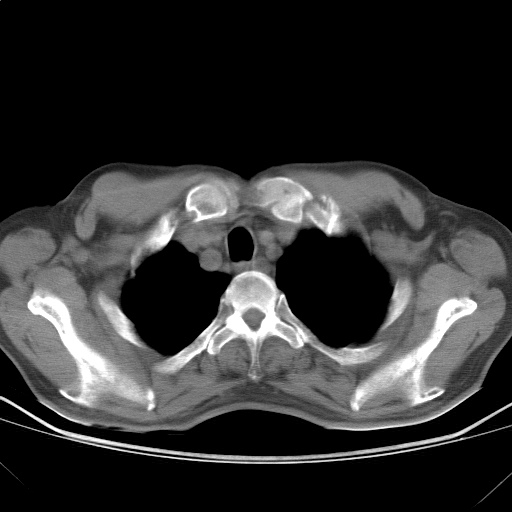

以下是引用随光逐影在2009-5-1 13:53:00的发言:[br]考虑为:1)两肺血行播散型肺结核;2)右肺下叶炎症感染。3)右侧胸膜增厚。